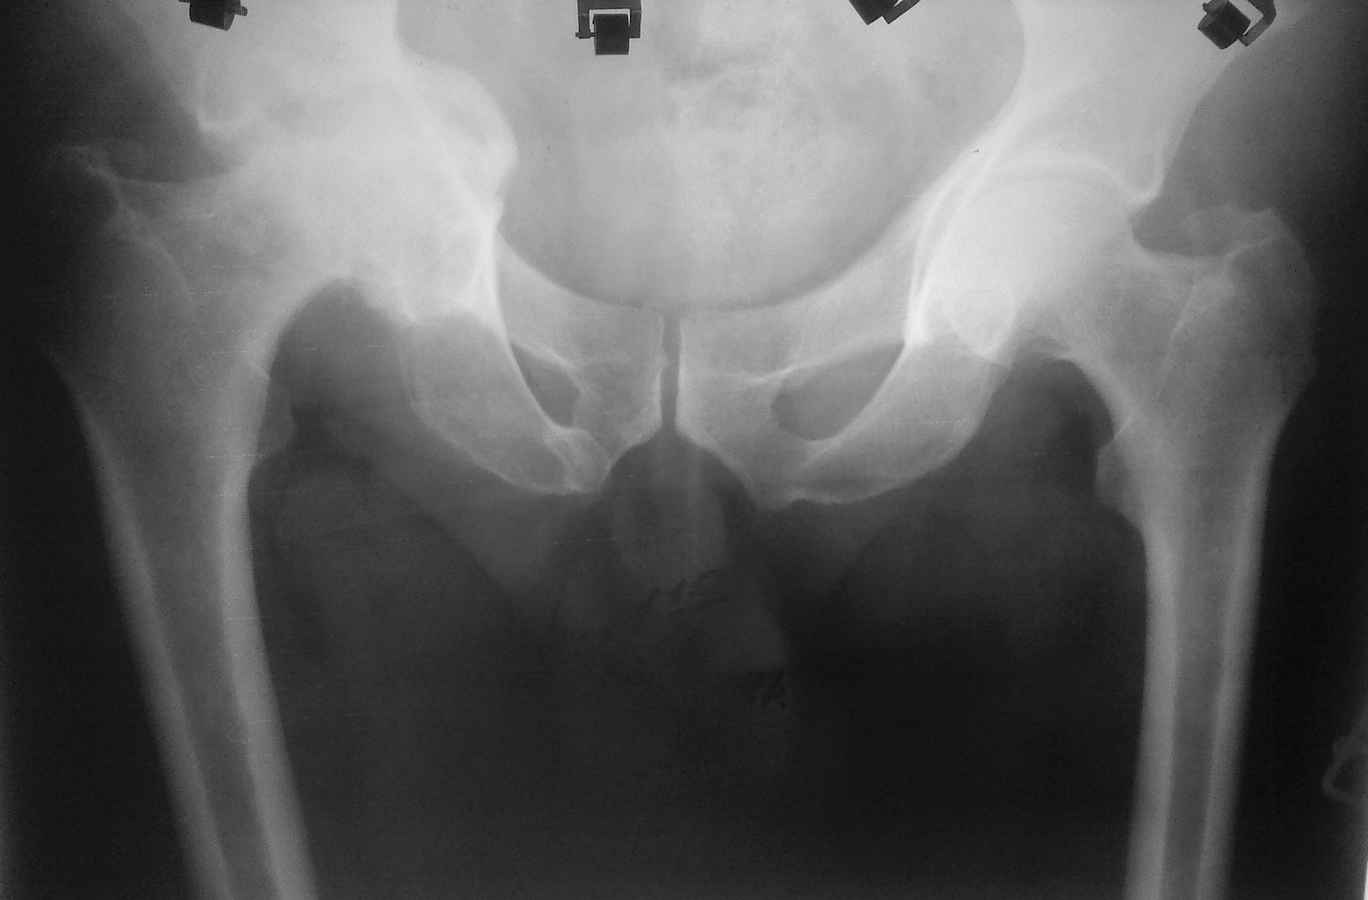

Здравствуйте. Уважаемые коллеги, поделитесь опытом у кого какая тактика при протрузионных

коксартрозах. У нас в клинике принято выполнять костную пластику дна стружкой из гололки, а

потом цементную чашку (снимки прилагаю). Выскажите свои взгляды на эту проблему,

пожалуйста.